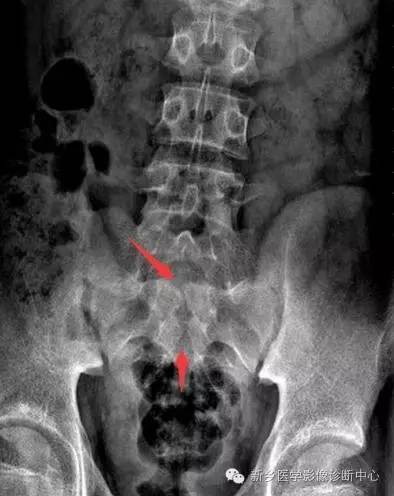

• 【病例】耻骨黏液型软骨肉瘤1例X线CT影像表现

【病例】耻骨黏液型软骨肉瘤1例X线CT影像表现